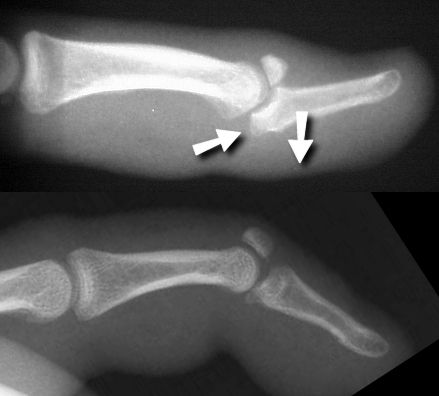

Figure Legend: Mallet fractures in which

the smaller fracture fragment includes half or more of the joint surface

may be unstable, resulting in palmar subluxation of the distal phalanx

(top). However, this is not always the case, and the joint may remain

stable despite a large avulsion fragment (bottom).